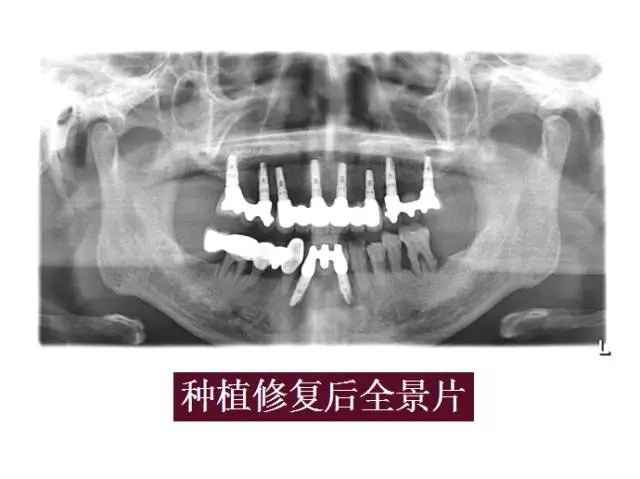

自體牙骨粉病例展示:

640.webp (6).jpg